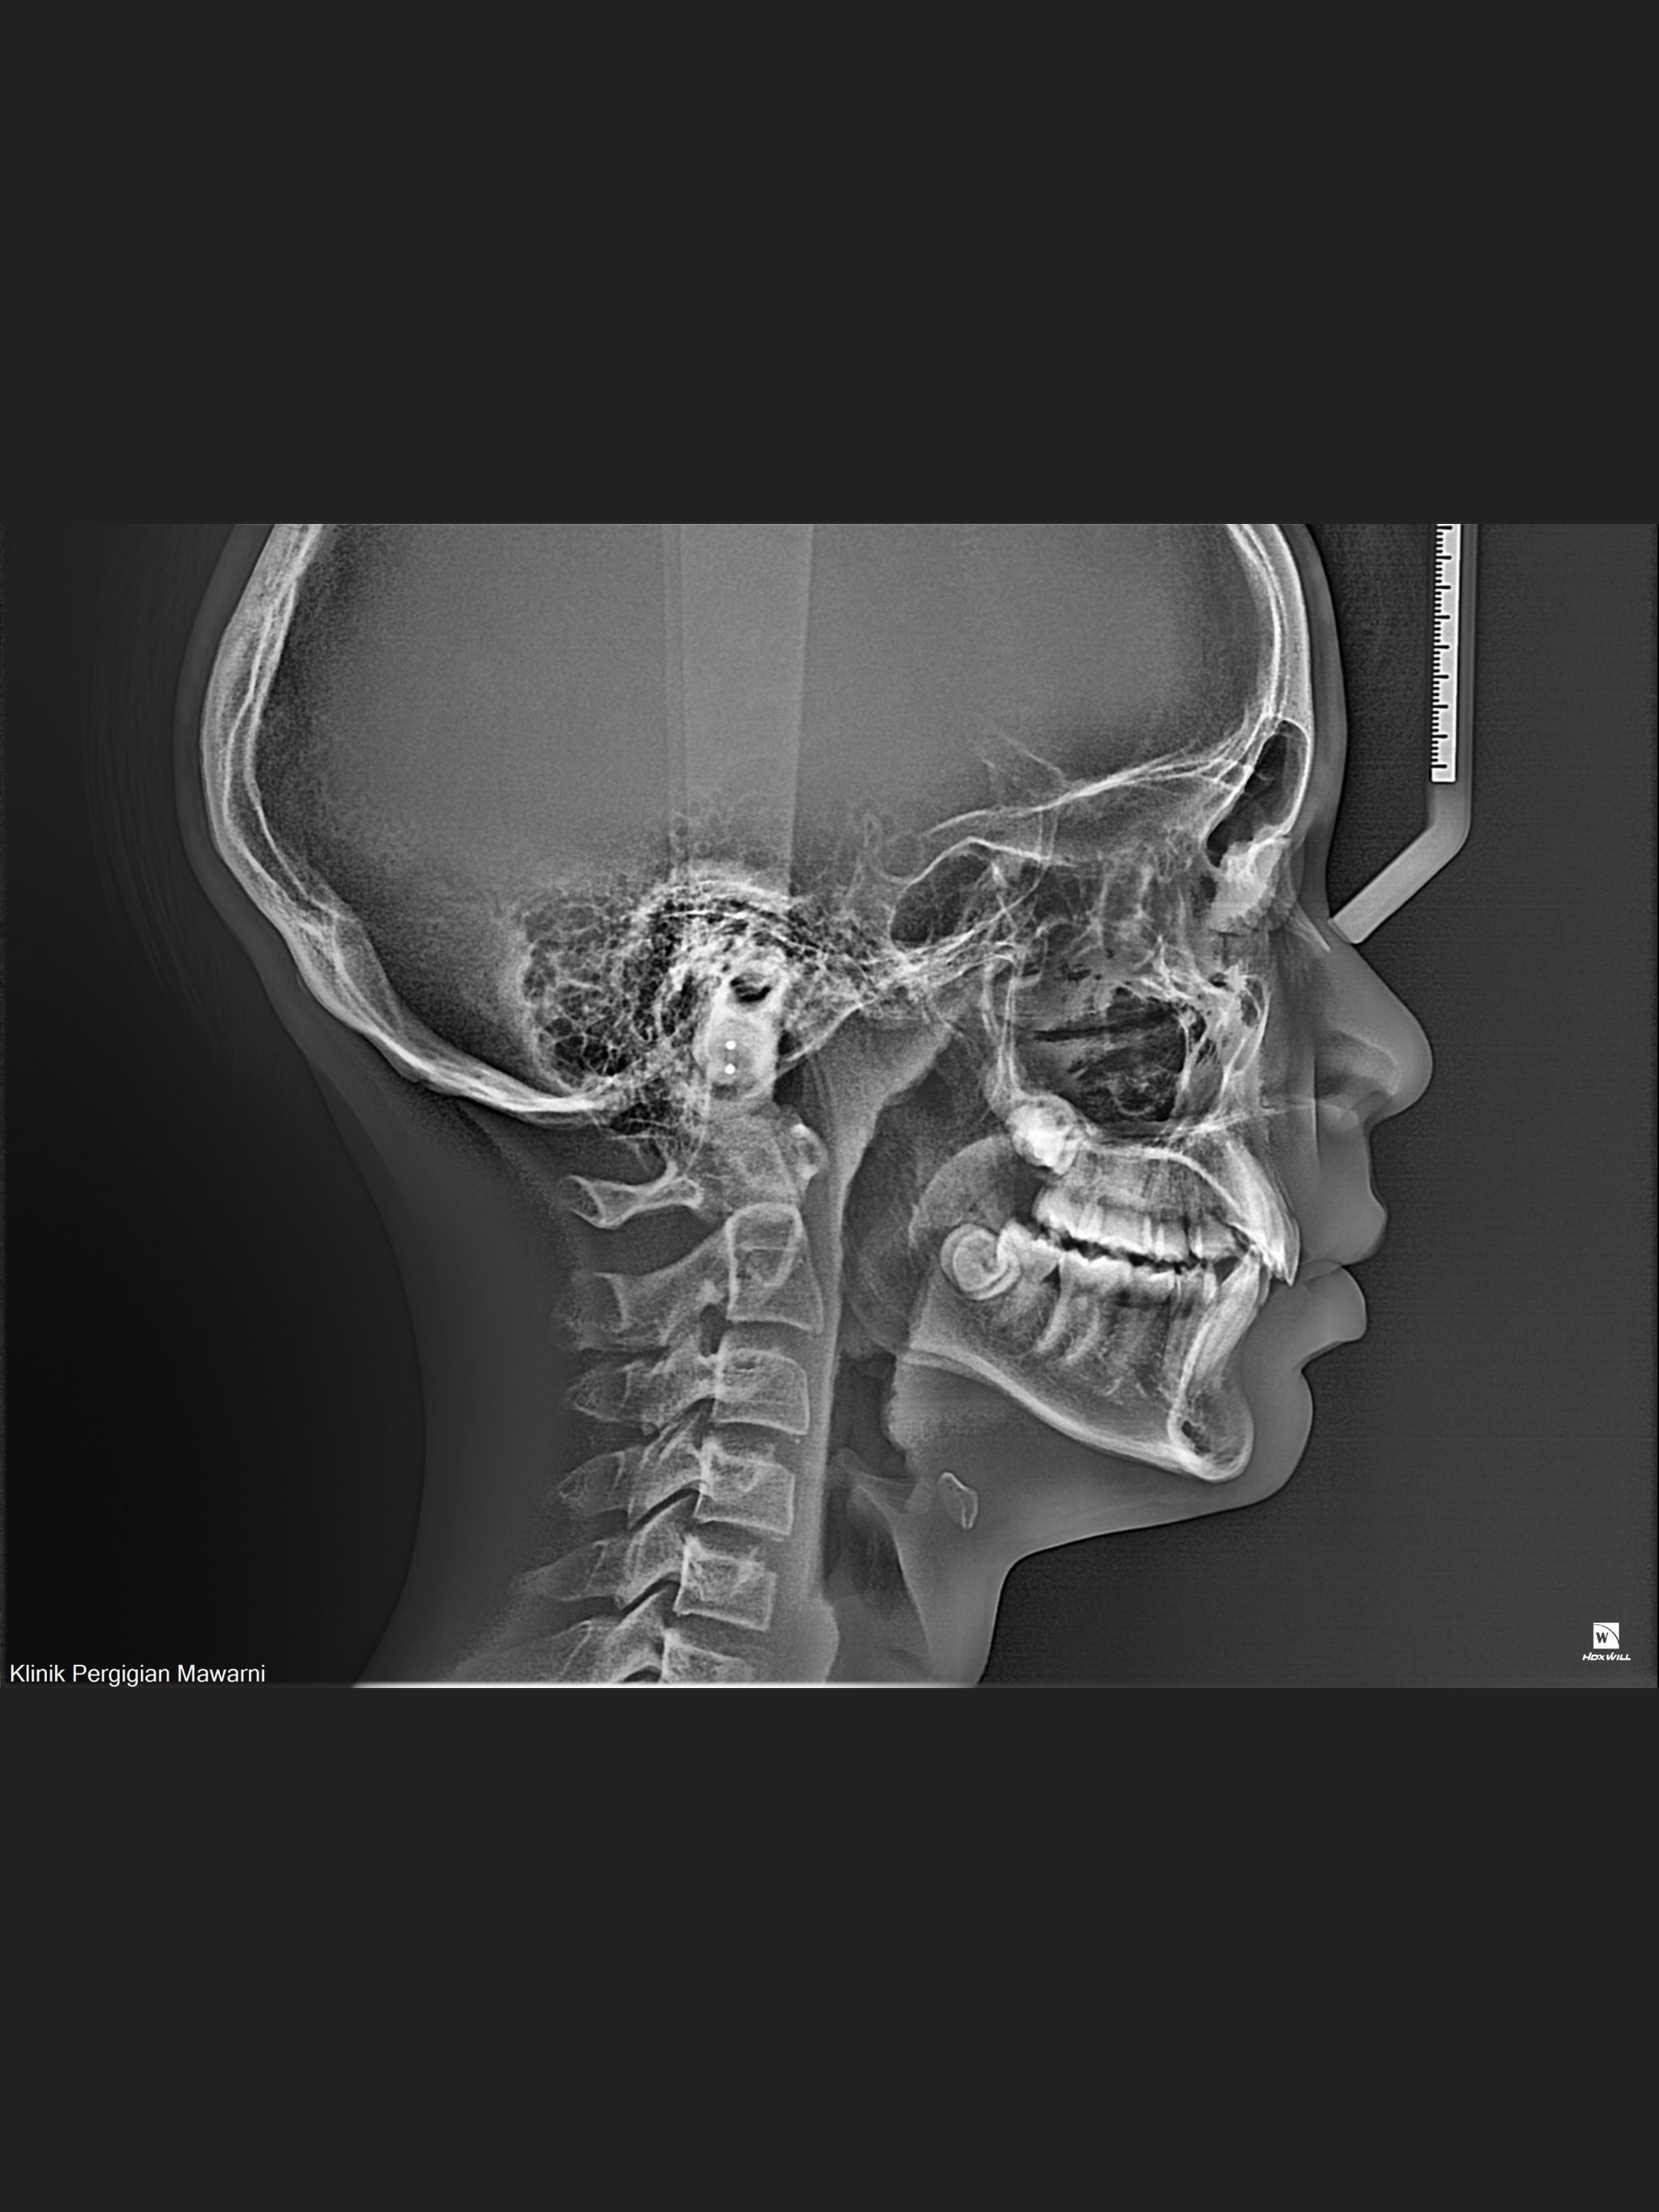

Our Lateral Cephalometric Image taken for mainly orthodontic (braces & aligner) patients.